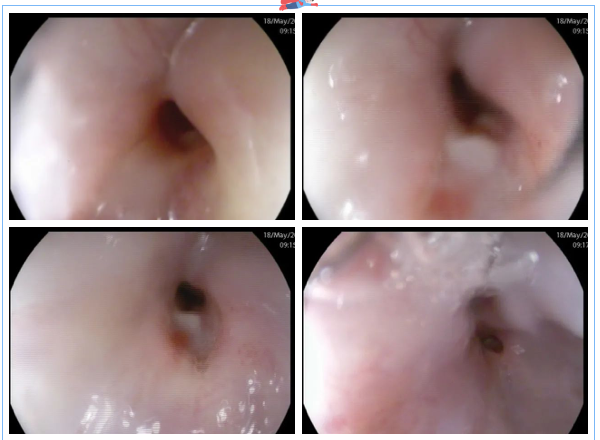

同時,7診是一位肝病患者,距門齒約28cm至齒狀線見數(shù)條深藍色隆起靜脈,扭曲呈結(jié)節(jié)狀,胃體、胃底黏膜充血水腫,呈蛇皮樣改變,散見片狀紅斑。食管靜脈曲張重度,門脈高壓性胃病癥狀明顯。